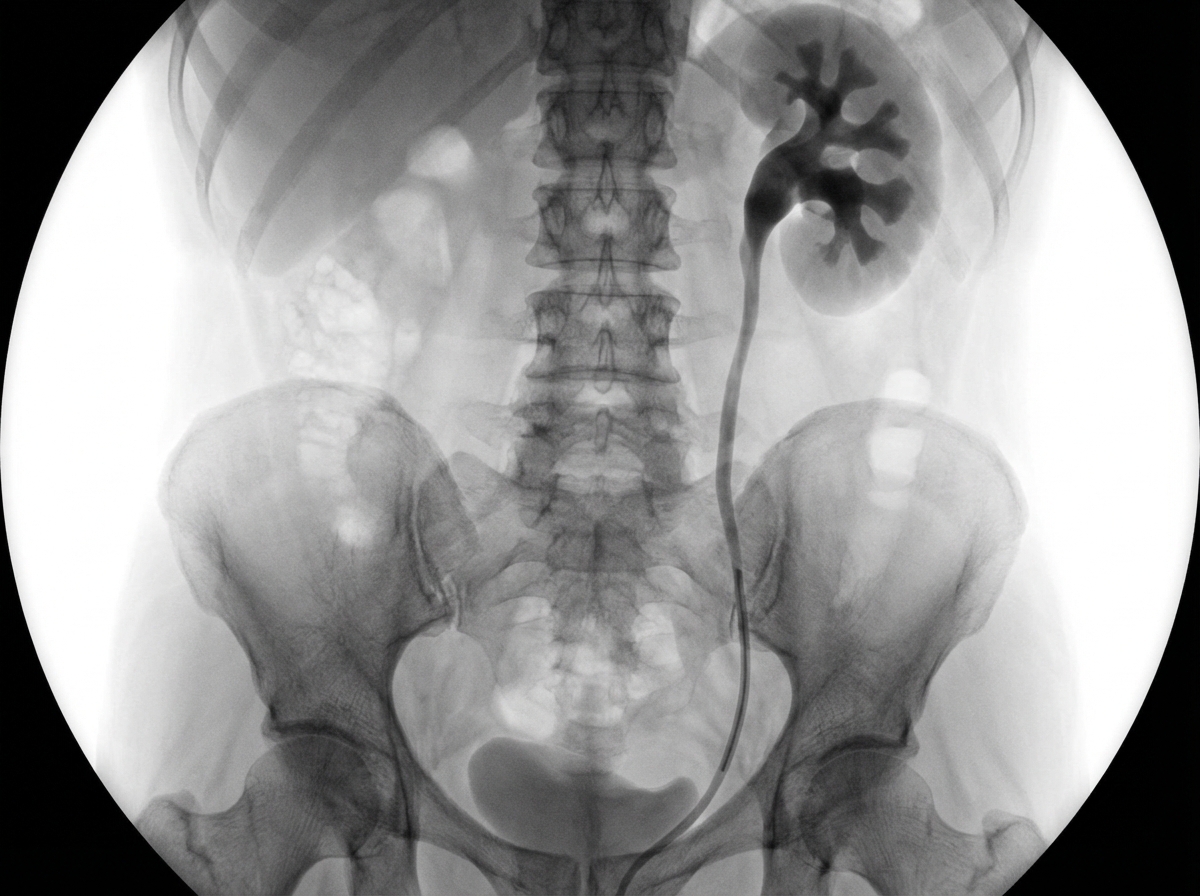

What is this study?

Explanation: ***Retrograde Pyelogram*** - Shows **contrast injected via ureteral catheter** with **pelvicalyceal system opacification** without nephrogram phase, characteristic of retrograde approach. - **Catheter visible** ascending from below through the ureter, confirming retrograde contrast injection technique. *Ultrasound* - Uses **sound waves** without any contrast material, producing grayscale images of organ structure. - Cannot demonstrate the **detailed pelvicalyceal anatomy** with contrast opacification seen in this study. *X Ray KUB* - Plain radiograph showing **bones and soft tissue shadows** without any contrast enhancement. - Would not show the **opacified collecting system** or ureteral catheter as clearly demonstrated here. *Contrast CT KUB* - Provides **cross-sectional images** in axial, coronal, and sagittal planes with contrast enhancement. - Would show **nephrogram phase** with parenchymal enhancement, unlike this study which shows only collecting system opacification.